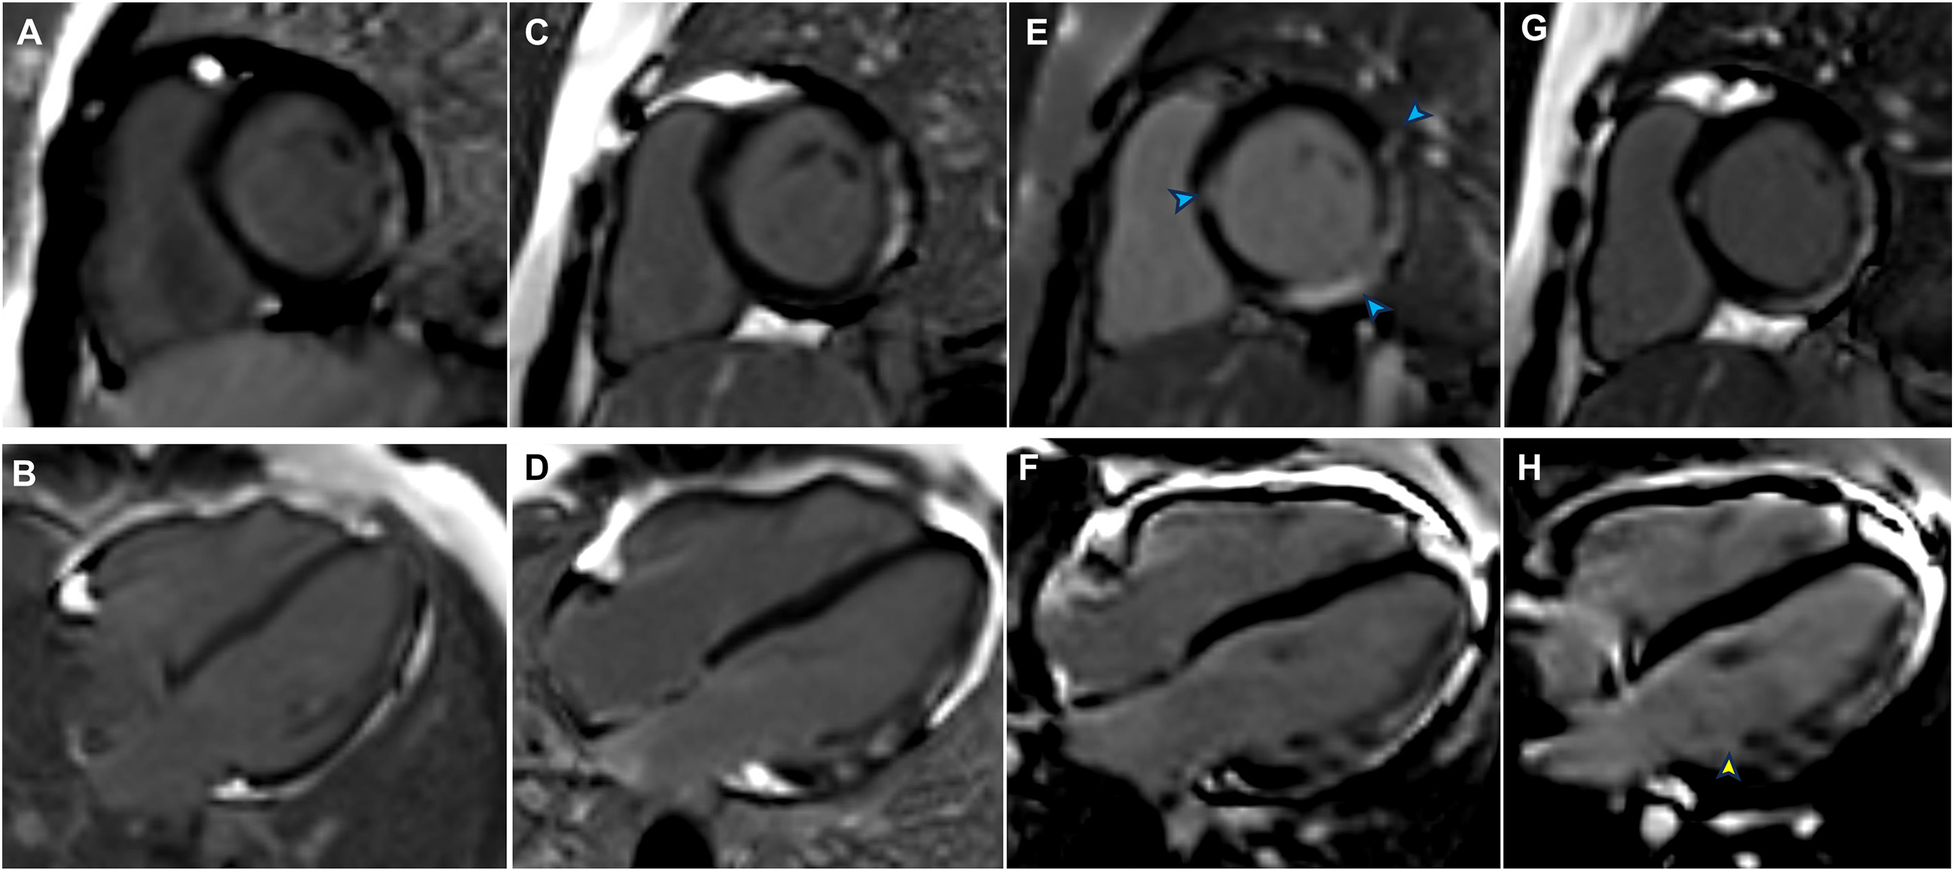

Figure 1

Late gadolinium enhancement (LGE) findings from previous follow-up, admission, and post-discharge follow-up. (A) LGE of the left ventricular (LV) lateral wall in August 2020 (LV short-axis views). (B) LGE of the LV lateral wall in August 2020 (LV long-axis views). (C) LGE of the LV lateral wall from the basal to middle segments in January 2023 (LV short-axis views). (D) LGE of the LV lateral wall from the basal to middle segments in January 2023 (LV long-axis views). (E) LGE was present in the interventricular septum and inferolateral lateral walls (blue arrowheads) at admission (LV short-axis views). (F) Progression of LGE in the inferolateral walls at admission (LV long-axis views). (G) LGE persisted in the interventricular septum and inferolateral lateral walls in July 2024 (LV short-axis views). (H) An increased extent of LGE was evident in the inferolateral walls (yellow arrowhead) in July 2024 (LV long-axis views).

Although the patient did not report any cardiac symptoms, the elevated cTnI levels and abnormal ECG findings indicated possible myocardial necrosis. Thus, a CMR examination was recommended. CMR showed inflammatory myocardial edema with localized T2 hyperintensity (T2 ratio, 2.4; T2 mapping, 56.9 ± 0.4 ms) in the inferolateral walls and interventricular septum from the basal to middle segments (Figures 3A,B). Additionally, LGE progression in the inferolateral walls and interventricular septum was observed, supporting a diagnosis of acute myocarditis (Figures 1E,F).

CMR, the gold standard for noninvasive diagnosis of myocarditis, is essential for confirming a diagnosis of myocarditis when cardiac troponin levels or ECG findings are abnormal. In the few reported cases of DMD-associated myocarditis, patients often presented with edema in the left ventricular free wall and corresponding LGE on CMR (8, 9). Abdul et al. found myocardial edema and LGE in both septal and lateral walls (8), consistent with our CMR results. Notably, our patient already had left ventricular free wall LGE before the onset of myocarditis. During myocarditis, however, the extent of free wall LGE increased; we also observed transmural LGE in the inferior wall and new interventricular septal LGE. The presence of transmural and septal LGE is presumably associated with a poor prognosis (15, 18).